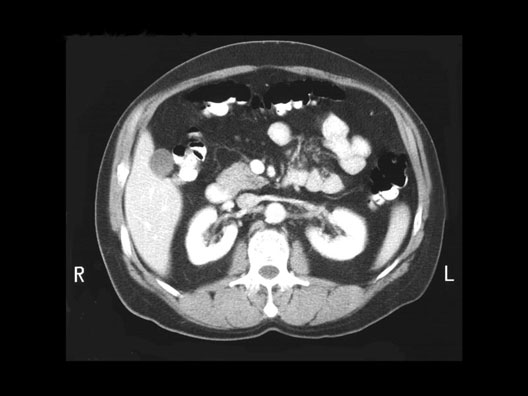

Renal Artery and Renal Vein

1. Inferior Vena Cava

2. Pancreas

3. Superior Mesenteric Vein

4. Transverse Colon

5. Superior Mesenteric Artery

6. Renal Vein

7. Pancreas

8. Left Colic Flexure

9. Spleen

10. Left Renal Artery

11. Aorta

12. Right Renal Artery

13. Duodenum

14. Gall Bladder

15. Hepatic Flexure